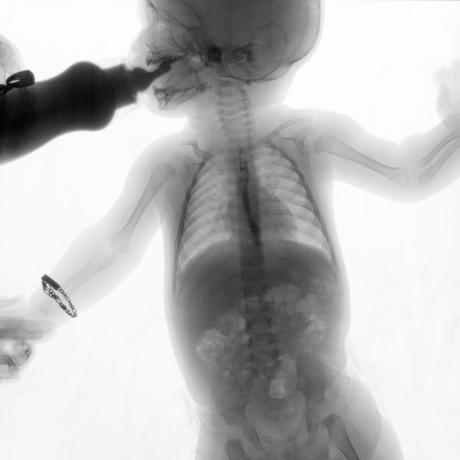

ESTUDIO SOLICITADO: SERIE ESOFAGOGASTRODUODENAL.

Se realiza Esofagograma con material de contraste baritado, por vía oral y por medio de control fluoroscópico se toman distintas proyecciones observando lo siguiente.

Se observa mecánica de la deglución con adecuado paso de medio de contraste de faringe a esófago sin presencia de defectos de llenado depósitos anómalos o fuga del mismo.

ESÓFAGO se observa de situación, calibre y trayecto normal. Contornos regulares y bien definidos. No se observan depósitos anómalos, defectos de llenado o fuga del medio de contraste.

UNION ESOFAGOGASTRICA se observa con calibre y situación normal. Sin observar reflujo a las maniobras de valsalva

ESTOMAGO se observa en su situación habitual, distendido, sin defectos de llenado.

- Actualmente no se demuestra Reflujo gastro-esofágico.

- Estudio de apariencia normal.